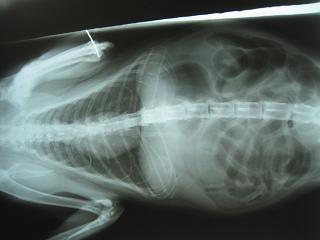

- 編號: 471

主題: 慢性肺炎和慢性拉肚子的卡拉貓 申請者姓名: 敏大哥 花色: 申請日期: 2012-06-27 00:23:20 申請者部落格: 申請者臉書網址: 所在縣市/合作醫院: 台北市/詠欣動物醫院 治療費用: 11430元 需求人數: 29人 已結案 (2012-12-01 20:33:22) 報名人員: philip(已付款)、Katty(已付款)、Lisa Fu(已付款)、Terence、慢慢、慢慢(已付款)、Vavina Kim(已付款)、紀昇志、紀昇志(已付款)、Angel、小菲(已付款)、Laura Hsu(已付款)、白娃娃(已付款)、姆姆(已付款)、boodan(已付款)、葉(已付款)、Kay Wang(已付款)、姿姿(已付款)、嘟嘟(已付款)、嘟嘟(已付款)、嘟嘟(已付款)、嘟嘟(已付款)、嘟嘟(已付款)、嘟嘟(已付款)、嘟嘟(已付款)、嘟嘟(已付款)、嘟嘟(已付款)、嘟嘟(已付款)、A喵(已付款)、白娃娃(已付款)、佳淳(已付款)、佳淳(已付款)、佳淳(已付款)、 候補人員: 小舟、小舟、 動物病情說明: 傳染病一直是貓場中難以解決的問題。平溪張媽媽目前致力處理貓場中拉肚子和肺炎的問題。卡拉貓最近一直掛著兩行鼻涕,呼吸也越來越快,拉肚子也是時好時壞。這群貓中,狀況較糟的.先送醫處理頑固的疾病.之後再將醫好的貓 分開飼養..